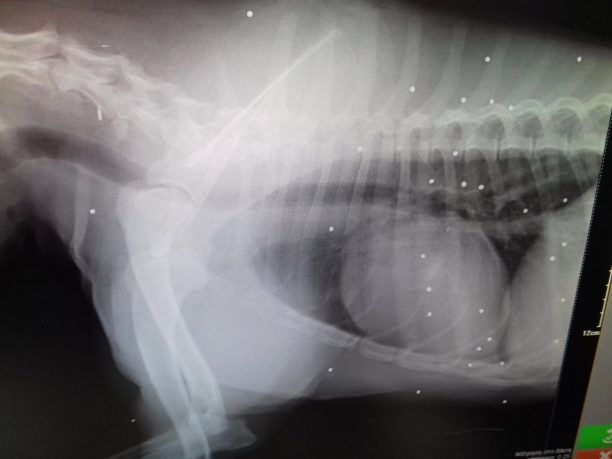

Στην ακτινογραφία που δημοσίευσε ο Φιλοζωικός Σύλλογος Ανθούσας – Γέρακα – Παλλήνης φαίνονται τα σκάγια στο κορμί του τραυματισμένου σκύλου που τον ονόμασαν Μπρούνο.